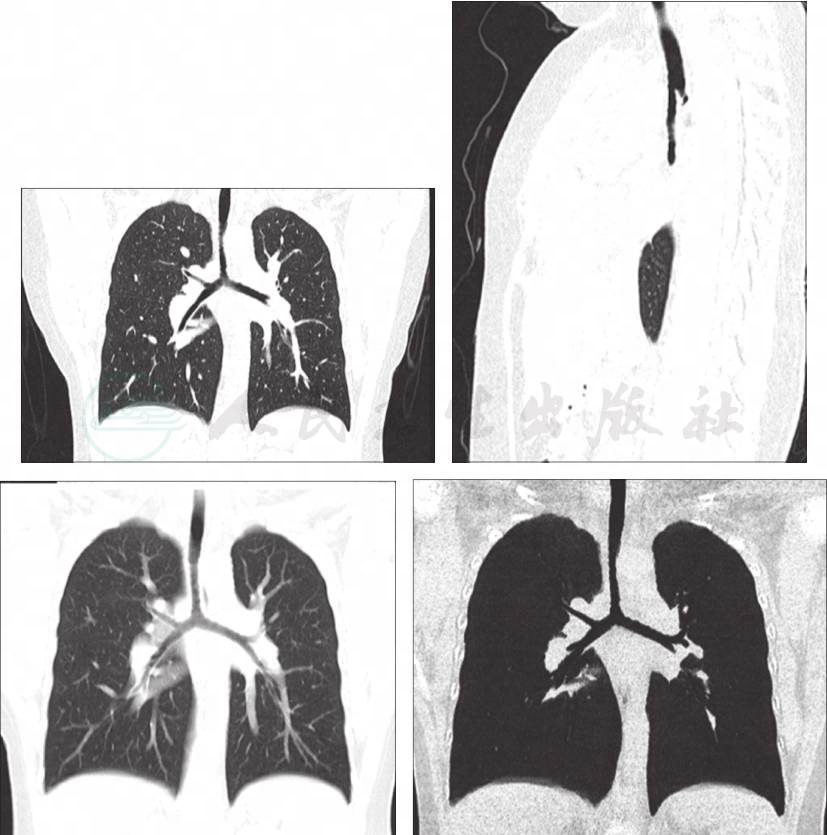

予患儿行喉镜及喉部CT检查正常,睡眠监测正常,故可除外鼻咽喉部结构异常。肺部CT+三维重建检查提示右肺气管中下段气管狭窄(图1)。因可疑气管狭窄,进而予患儿行局麻下纤维支气管镜检查,术中发现,患儿左肺下叶B6开口缺如,右肺上叶B3及右肺下叶B7开口形成盲端,右侧气管中下段气管轻度狭窄(图2)。因此诊断明确,患儿反复气促为先天性气管发育畸形所致。

图1 肺部CT+三维重建检查

提示右肺气管中下段气管狭窄

诊断依据:有反复发作的活动后气促症状;发作时肺部查体闻及呼气相干鸣;肺CT三维重建提示右侧气管狭窄,纤维支气管镜检查明确气管狭窄,同时发现气管发育异常,左肺B6开口缺如,右肺上叶B3及右肺下叶B7开口形成盲端;已除外其他心血管疾病、喉部发育异常等。